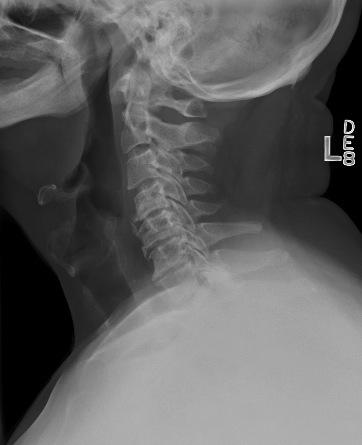

1. A 79-year old man falls sustaining a hyperextension injury to his neck. A lateral radiograph, CT scan and MRI are seen in Figures A through C. On motor examination, he has 3/5 strength in his deltoids, elbow and wrist flexors and extensors. He has 4/5 strength in his hip flexors, knee flexors, extensors, ankle dorsiflexors and plantarflexors. Sensation is preserved in both his upper and lower extremities as well as his sacral segments. Injury to which of the following tracts contributes greatest to his motor function deficits?

FIGURES: A

B

C

DISCUSSION: The clinical scenario describes a patient with central cord syndrome, resulting in an injury to his lateral corticospinal tract. Figures A through C show a spondylytic spine with central narrowing and CSF effacement that is worse at the C4-5 level. The lateral corticospinal tract is the main descending motor tract (Illustration A). Its anatomic position places the upper extermity motor tracts at greater risk than the lower extremity tracts. As such, injury to the lateral corticospinal tract is characterized by upper greater than lower extremity involvement and motor deficits being more pronounced than sensory deficits.